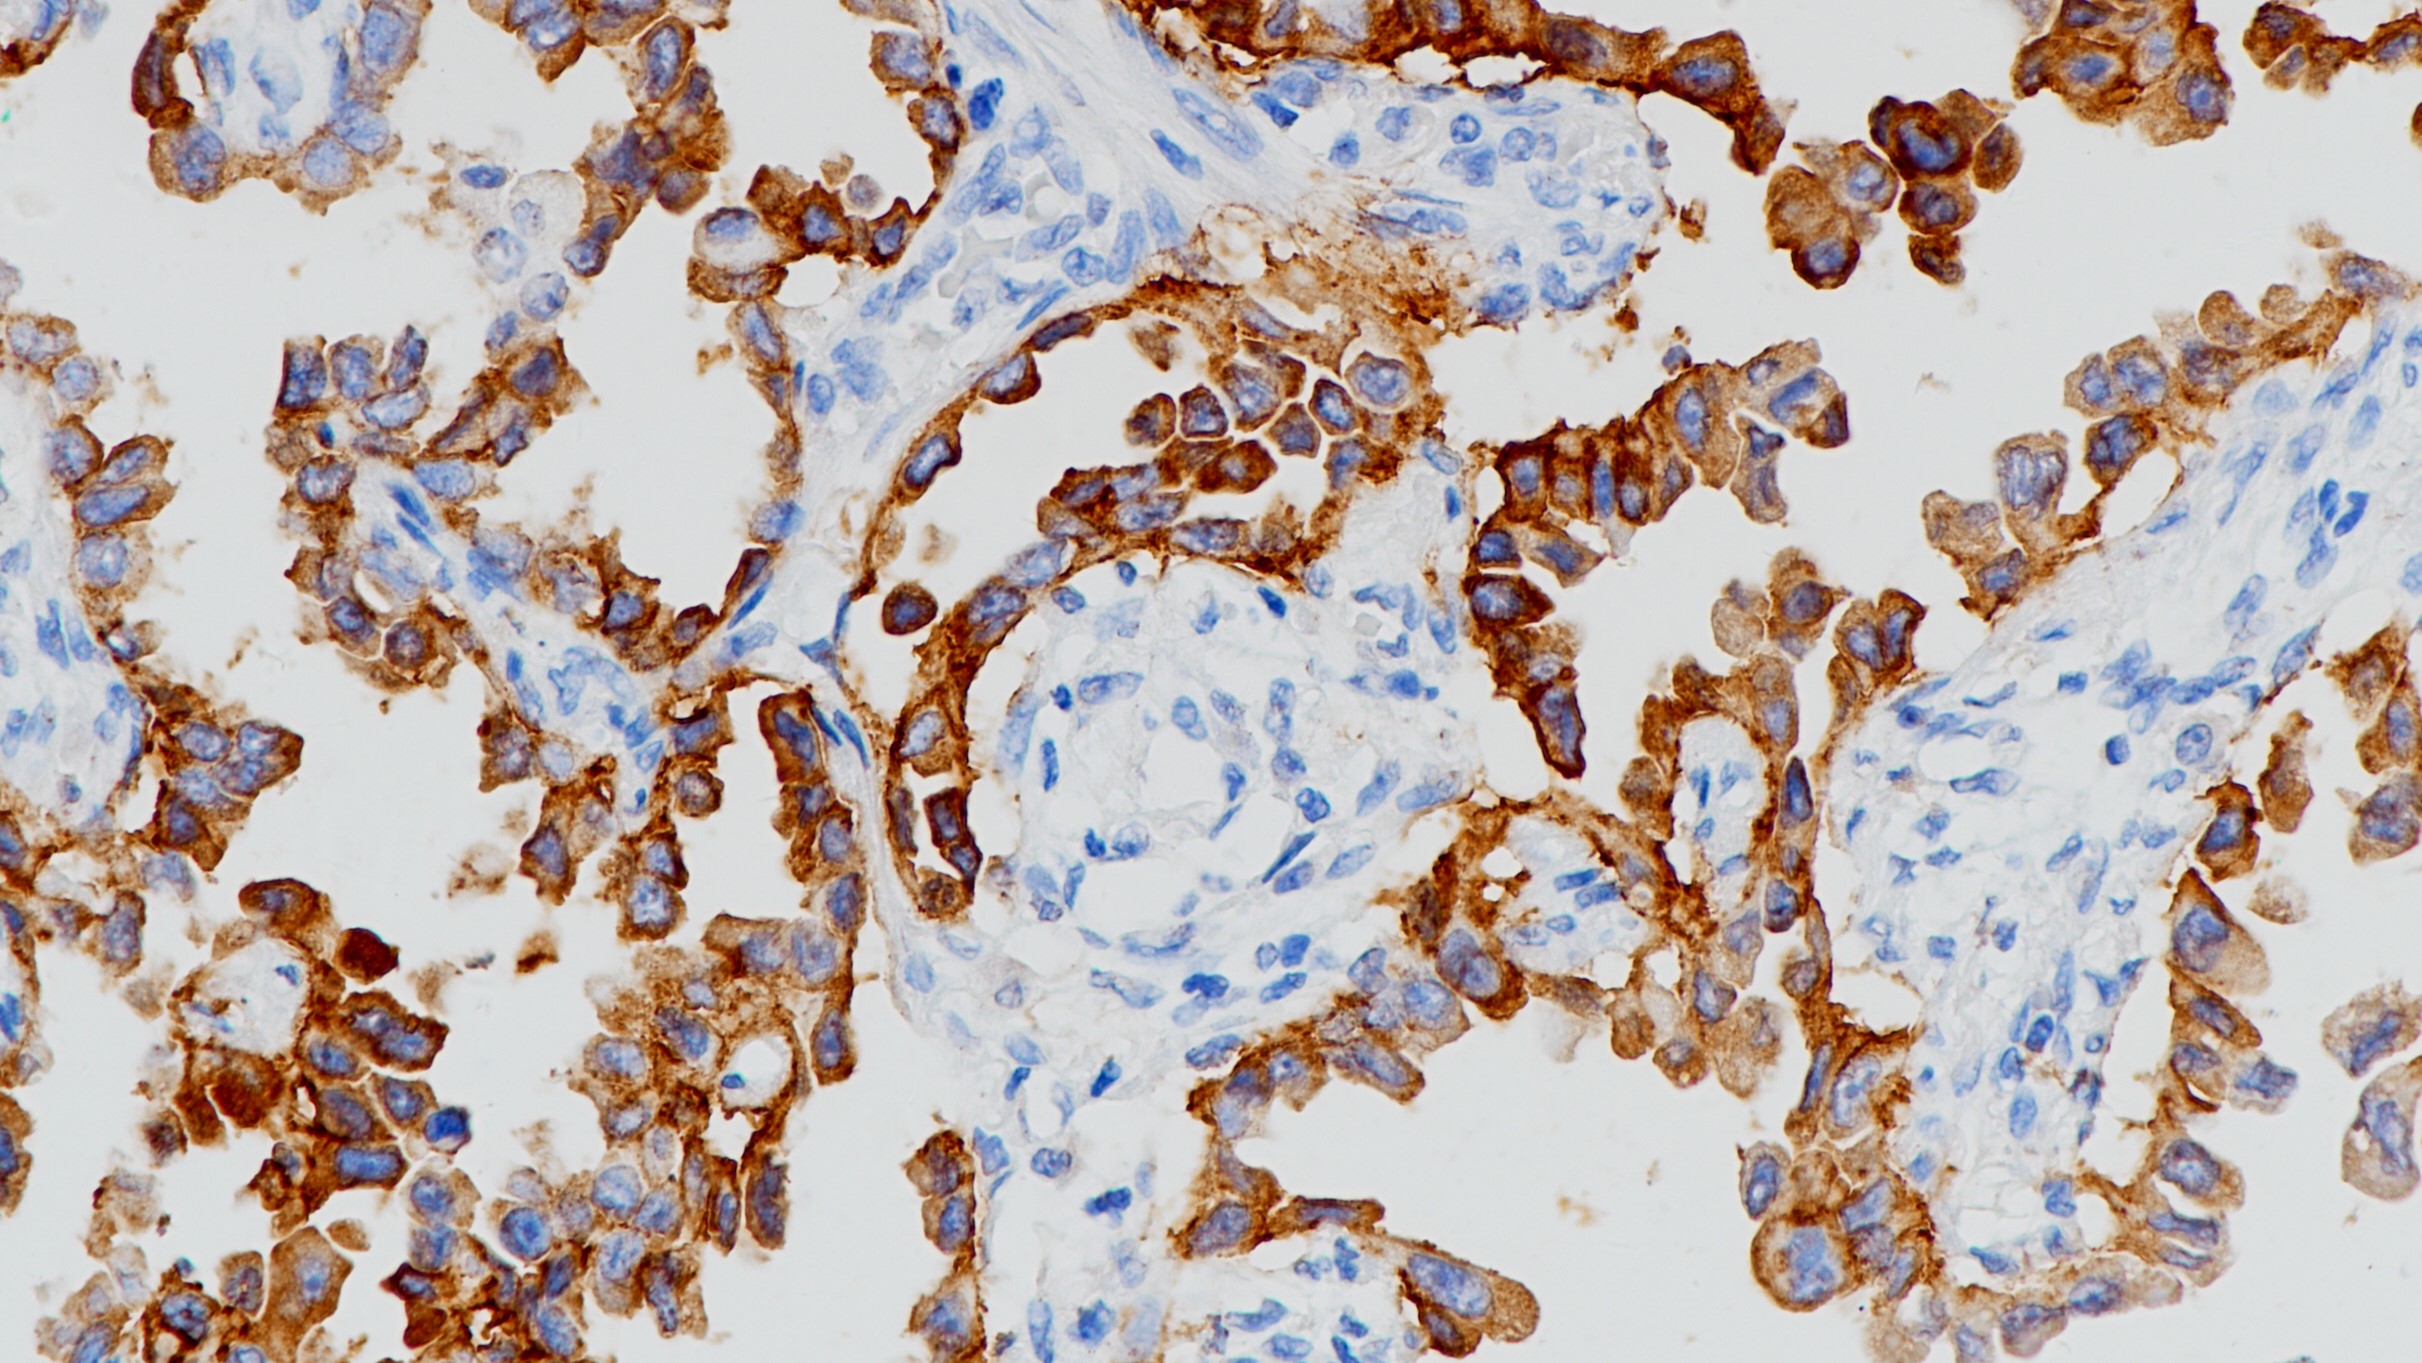

CD14即脂多糖(LPS)受体,在单核细胞和巨噬细胞中强表达,而在中性粒细胞上表达较弱。CD14通过糖基磷脂酰肌醇(GPI)锚定于细胞膜,其功能是作为LPS和LPS结合蛋白复合体的高亲和受体。可溶性CD14也可与LPS结合,在生理浓度下可作为LPS受体的诱导剂,而在高浓度下LPS 对细胞活化有拮抗作用。

CD14抗体试剂(免疫组织化学)

细胞膜

阳性对照

阑尾